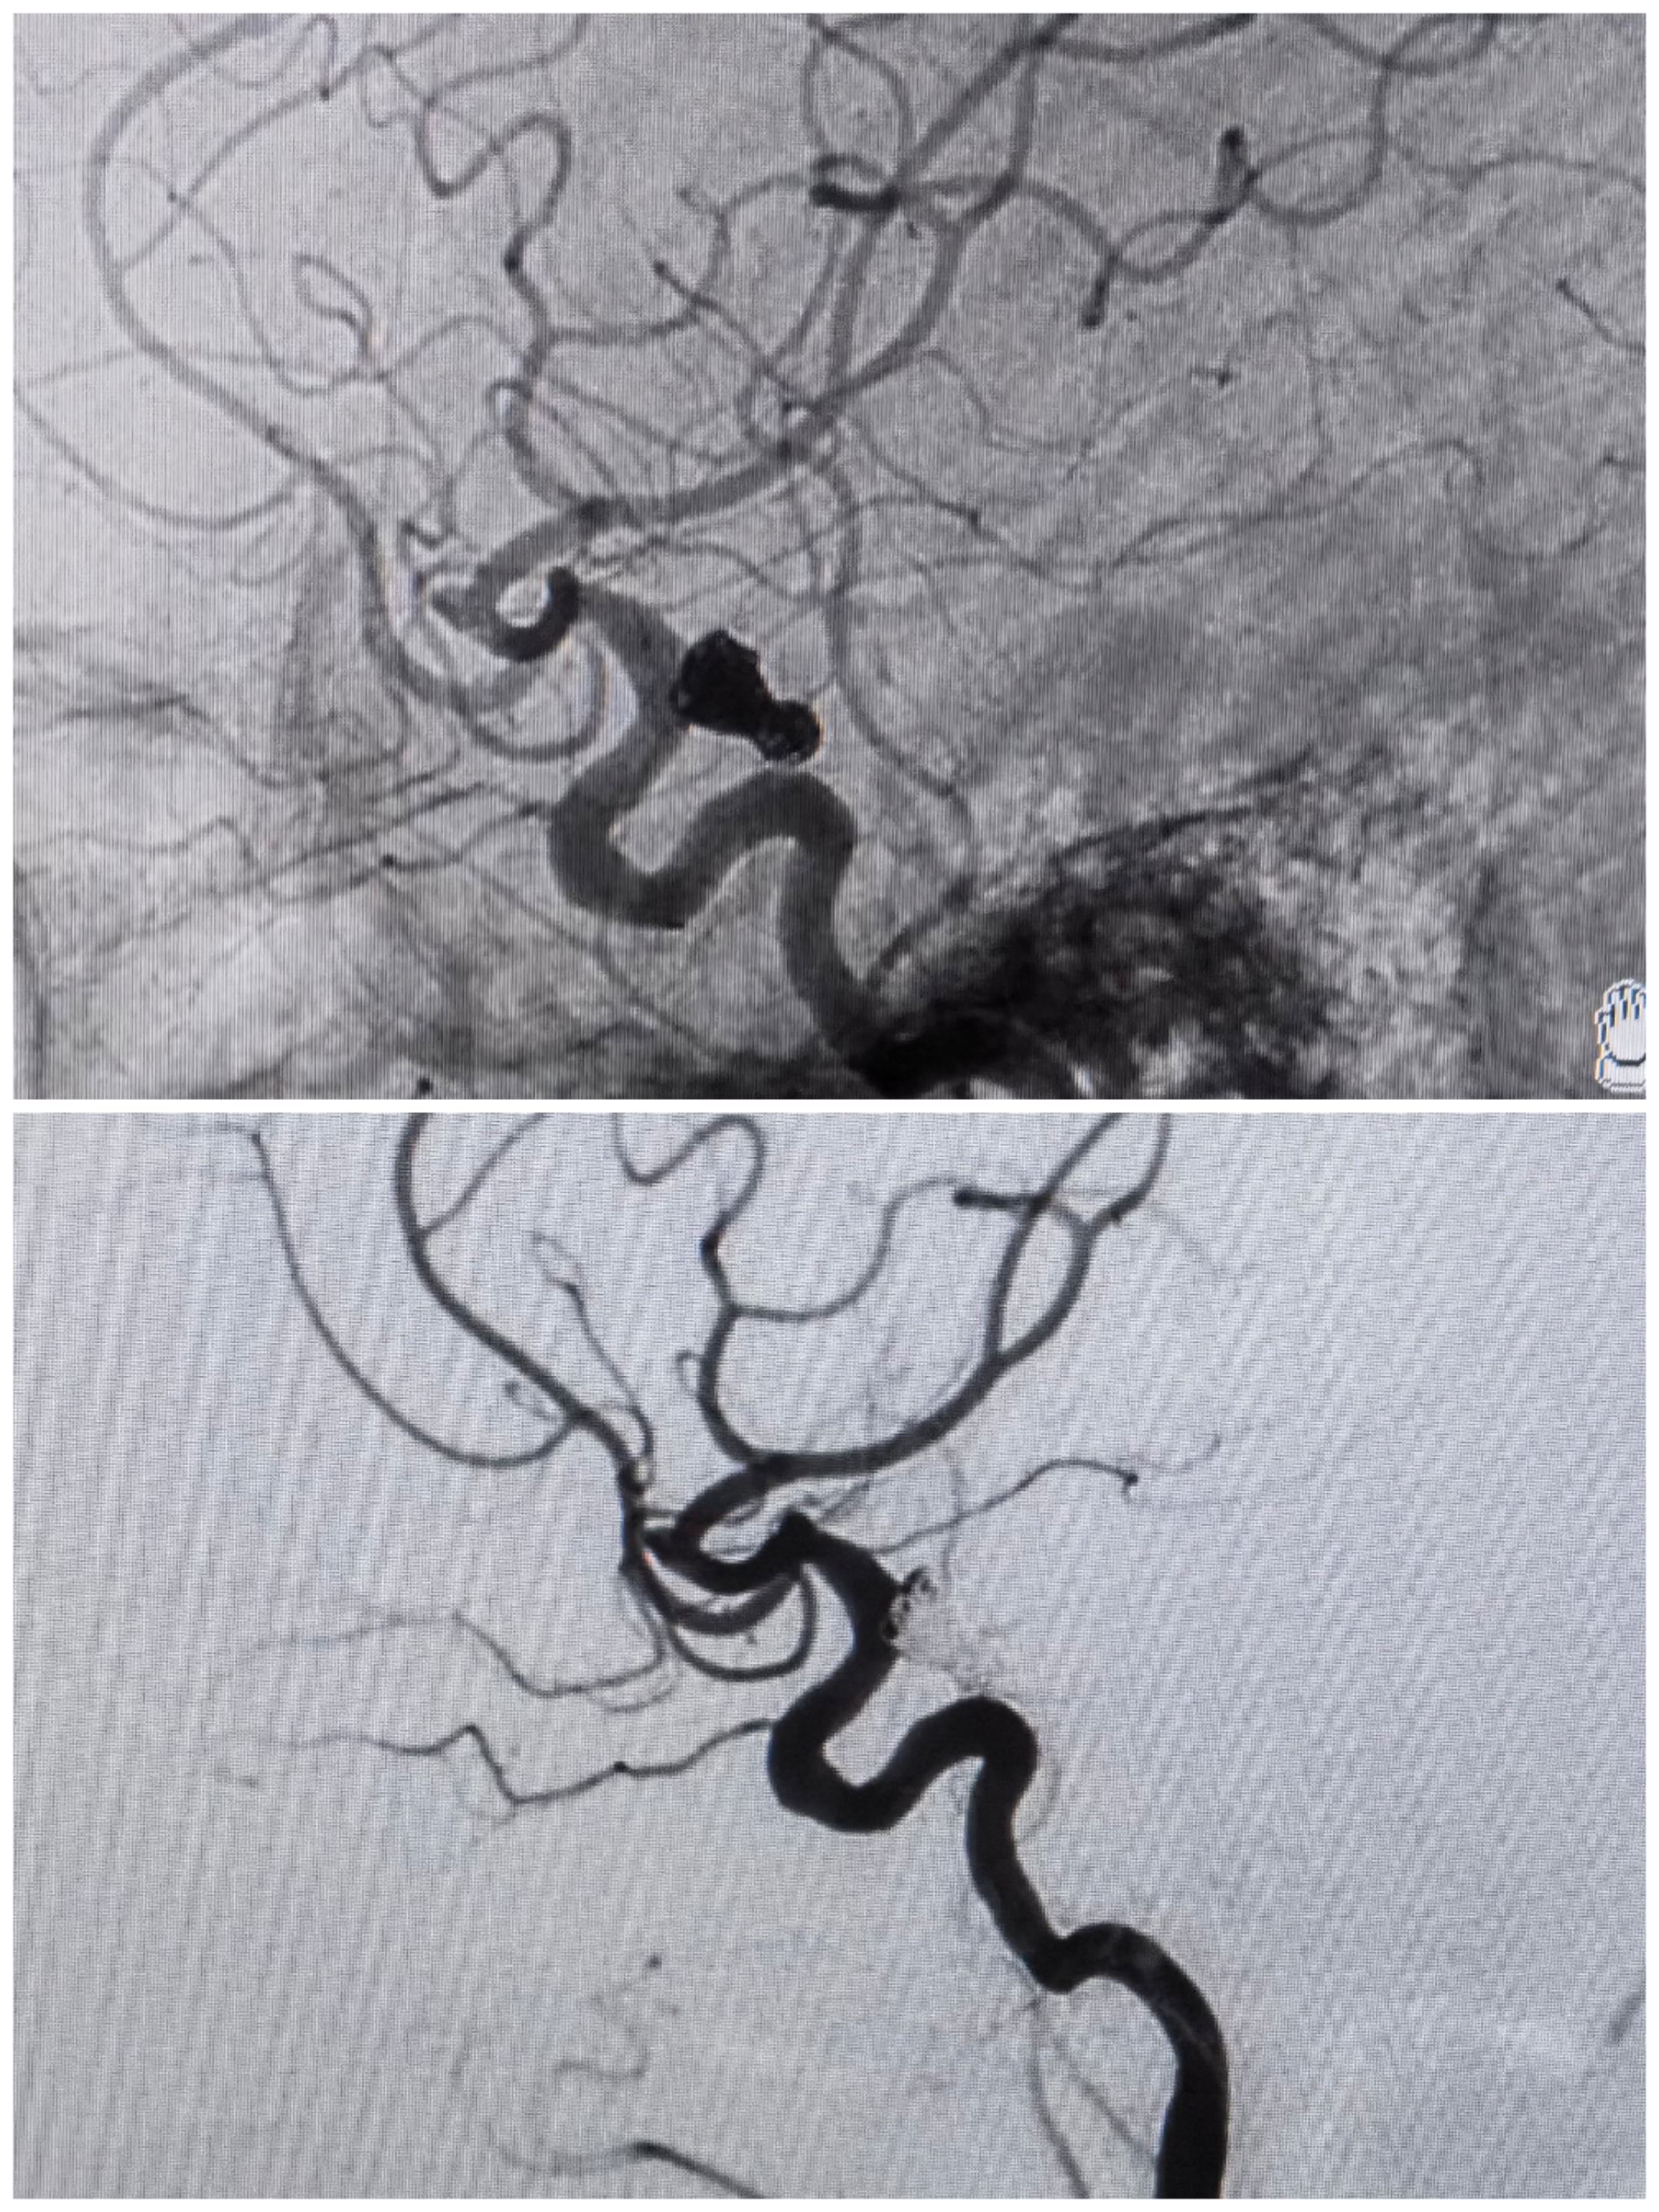

术前造影

术后工作位造影

术后3D旋转

术后3D重建